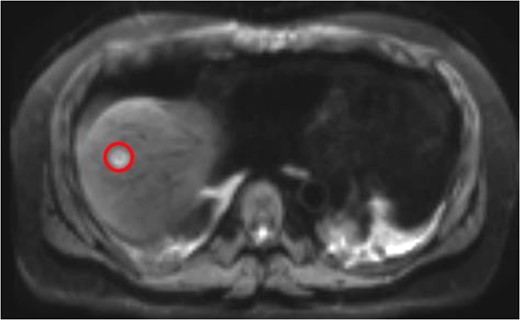

Colonoscopy revealed inflammatory polyps and an ulcerated circumferential mass 30 cm from the anal verge and positive for SCC. Positron emission tomography/computed tomography showed radiotracer uptake in the colon anastomosis, transverse colon, inferior mesenteric artery stump and mesenteric lymph nodes (Figure 1). A 2-cm liver segment VIII lesion was positive for SCC on core needle biopsy (Figure 2).

Liver Metastasis. The red circle indicates the 2-cm site of metastasis.

Magnetic resonance imaging (MRI) after the initial chemotherapy cycle demonstrated a liver segment VIII 13-mm metastasis and indeterminate 5-mm lesions in segments VI and IV. Interventional radiology services performed a right portal vein embolization. On subsequent postembolization MRI, hepatic lesions were indiscernible, and liver remnant volumetrics increased from 21 to 35%.